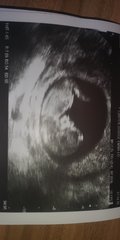

@Avocuddles my not so little Pip the ninja... Along with a bump pic from today. Had to tell folk really. Now way of hiding it anymore and was running out of excuses not to see people haha x

@SammiLou2312 hehe I love the little ninja kick!

@TunnocksTcake the kick photo is my favourite 🥰

Picture of the goblin and of Giovanni Perniche from the show tonight, so pleased that a few of us have had a good day

Naww beautiful pic @knotemma x

Aww thanks @SammiLou2312, I love you're little ones ninja kick! And your bump is gorgeous... I just look like I've eaten too much white bread! It's all just pudge and bloat 😂 finding an outfit for this evening was a challenge.